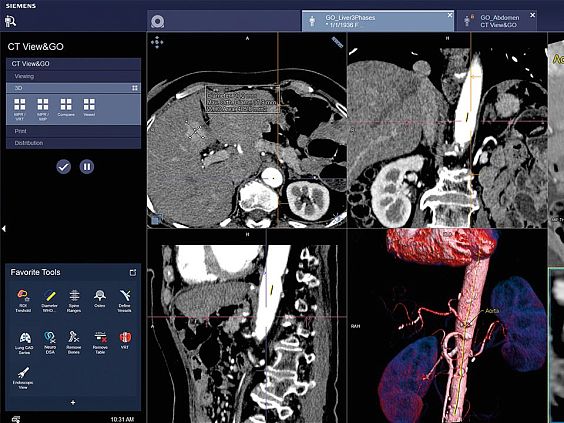

- Лёгкий планшет с высоким разрешением экрана дает полную свободу в организации работы

- Благодаря технологии Scan&GO для выполнения всего сканирования требуется лишь несколько шагов

- Вы можете проверить информацию о пациенте, как только пригласите его на исследование, и сразу же планировать сканирование на планшете, не отходя от пациента

- Приложение для планшетных компьютеров, предназначенное для дистанционного управления сканированием

- Возможность управления томографом из процедурной или другого помещения

- Автоматическая постобработка в рамках запланированных задач реконструкции

- Эта технология позволяет получать готовые для анализа и интерпретации изображения и сокращает количество этапов рабочего процесса

- Универсальное комплексное решение для большого количества востребованных клинических приложений

- Инструменты быстрого анализа в рамках единого рабочего процесса

- Конфигурируемый интерфейс под индивидуальные потребности пользователя